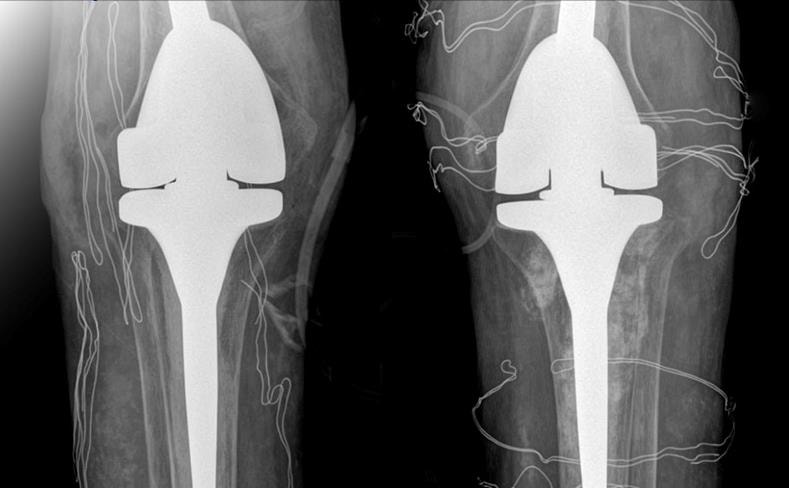

ThS.BS Nguyễn Quang Tôn Quyền, Phó khoa Chấn thương Chỉnh hình chẩn đoán nam bệnh nhân mất khả năng duỗi khớp gối, chỉ co được 60-70 độ, chụp X-quang cho thấy hai khớp gối bệnh nhân biến dạng nặng, tổn thương tophi khiến khớp và xương tiêu.

Phim chụp X-quang hai bên khớp gối nhân tạo của bệnh nhân. Ảnh: BVCC

Các bác sĩ đã tiến hành phẫu thuật thay khớp nhân tạo. Xét nghiệm máu trước mổ cho thấy nồng độ cortisol và ACTH (hormone kích thích tuyến thượng thận sản xuất cortisol) thấp. Bác sĩ chẩn đoán bệnh nhân bị suy tuyến thượng thận do lạm dụng chất dexamethasone dài ngày.

Êkíp bác sĩ loại bỏ các hạt tophi gây cản trở vận động, thay thế khớp gối đã tổn thương bằng loại khớp nhân tạo có bản lề, dành riêng cho bệnh nhân có các biến dạng khớp nghiêm trọng.